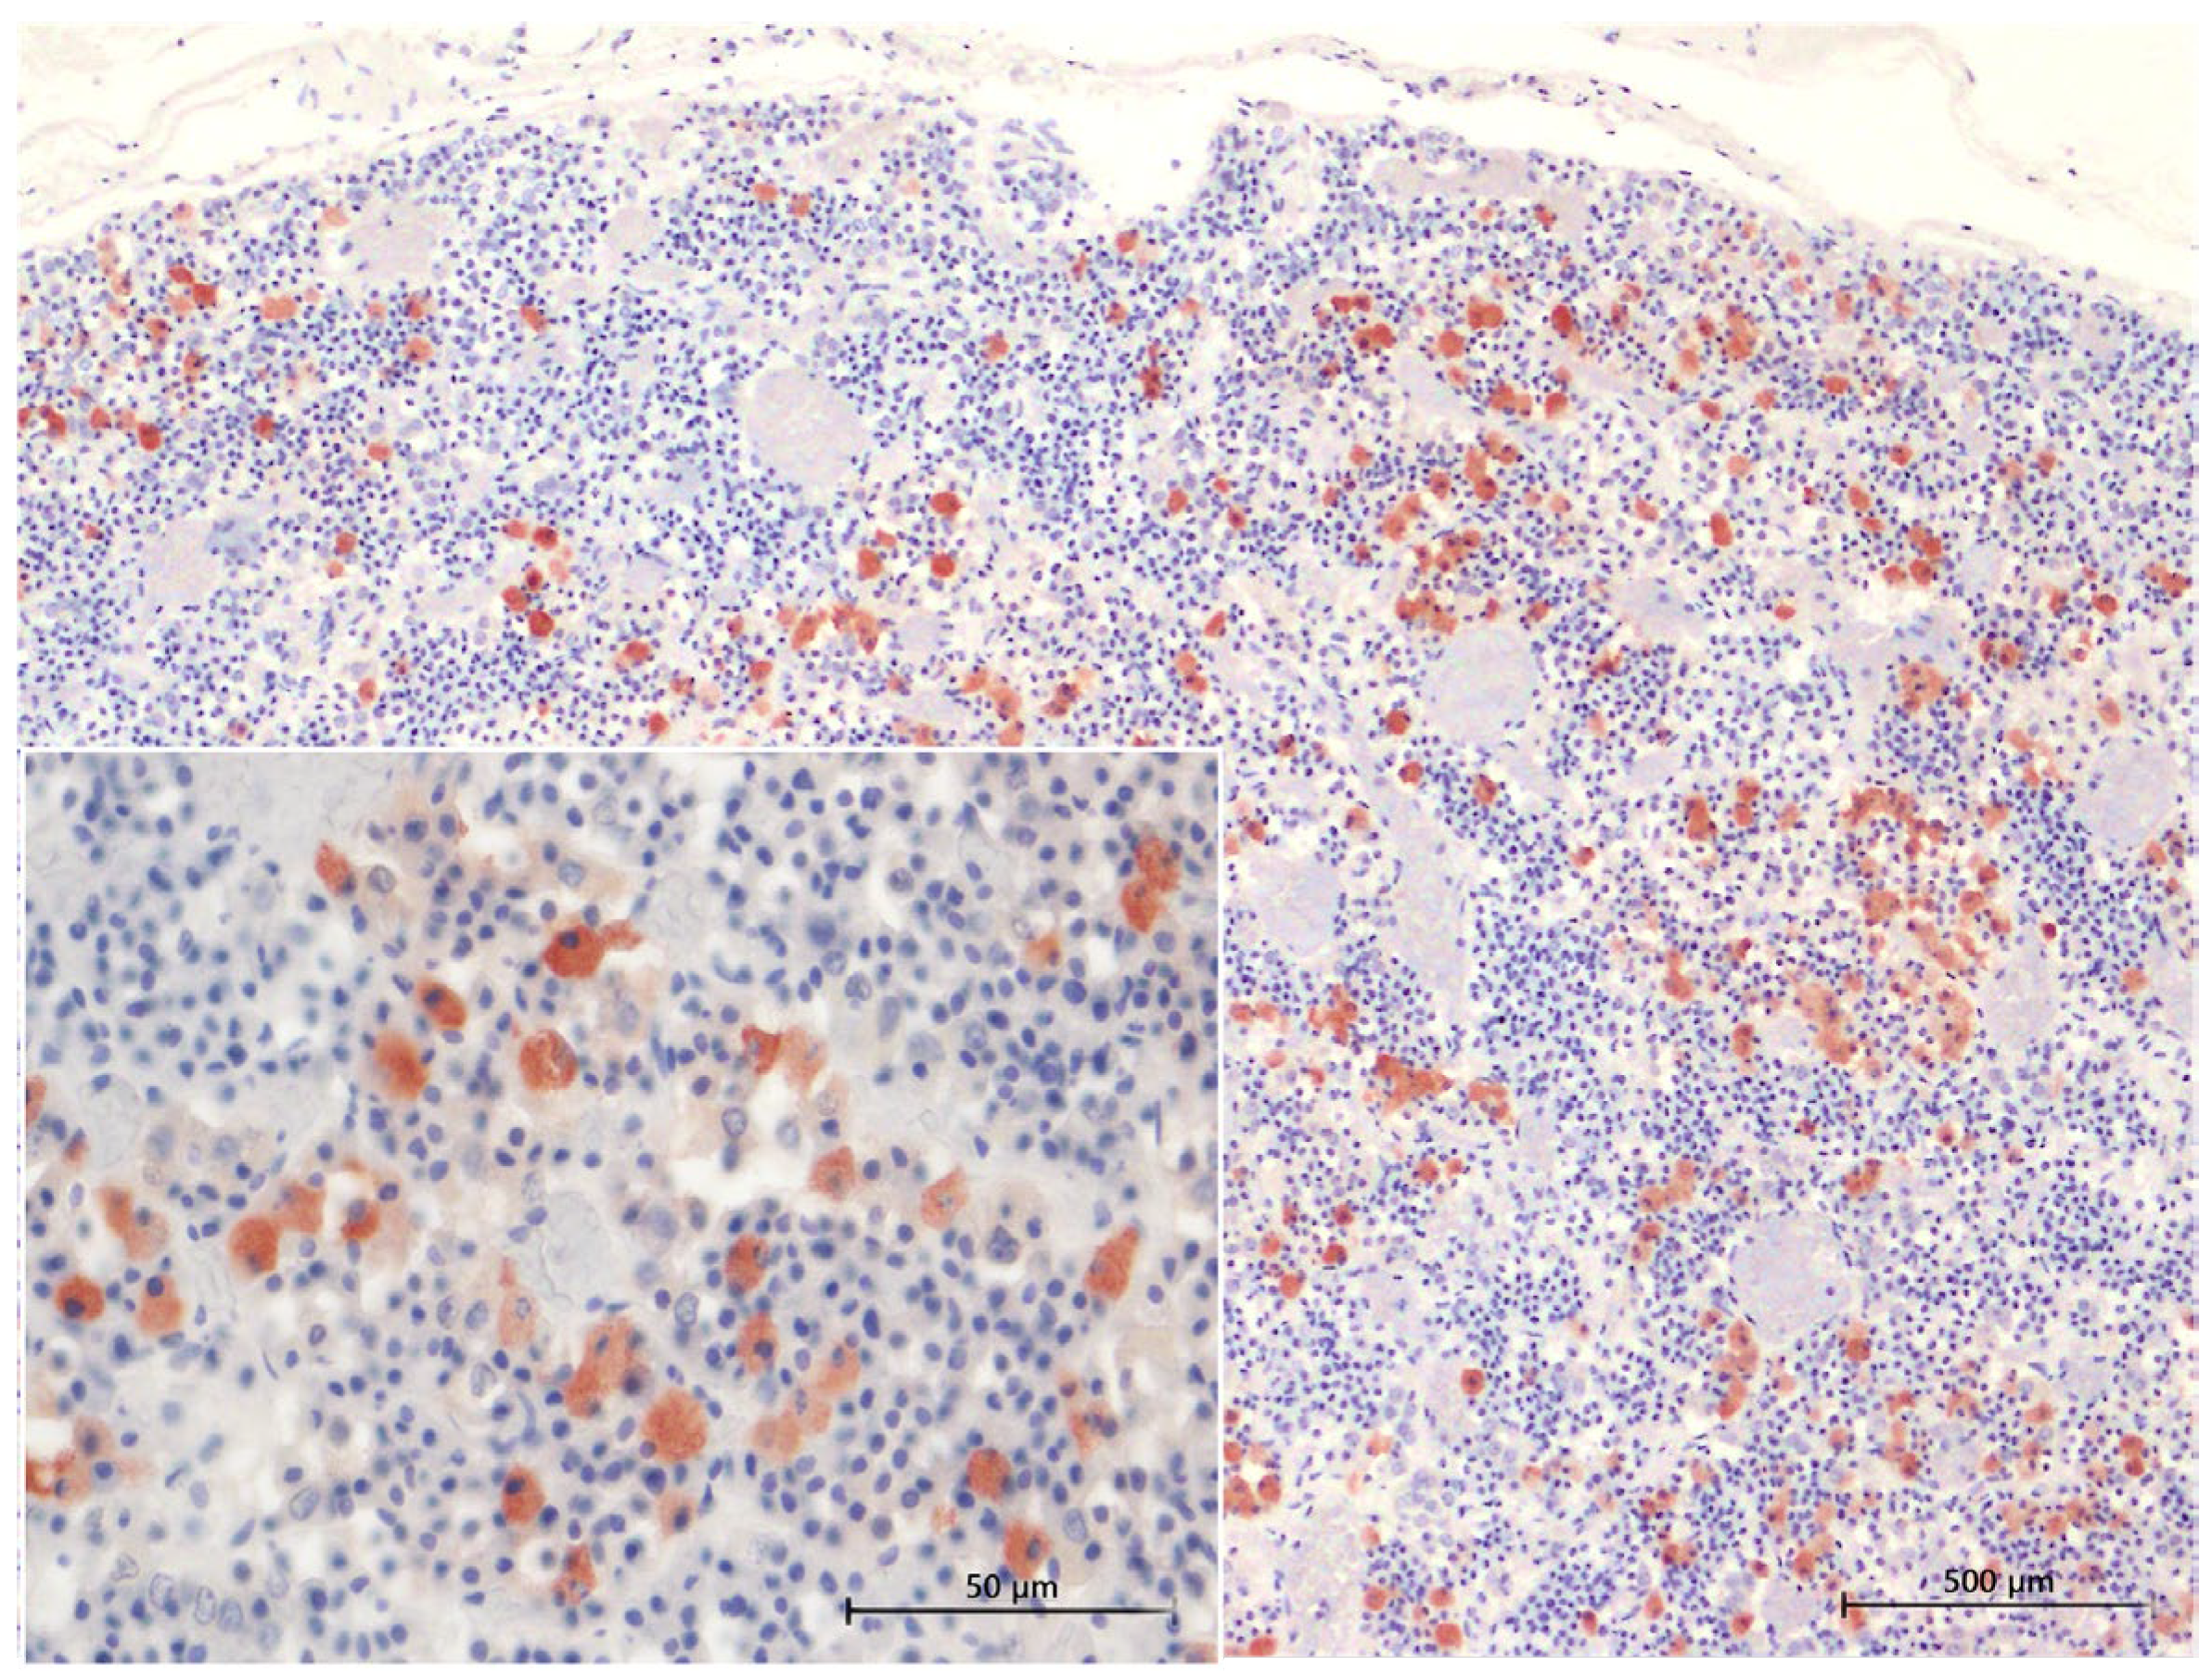

3.4. Inmunohistochemical Study

3.4.1. ACTH Labelling

3.4.2. MSH Labelling

3.4.3. TSH Labelling